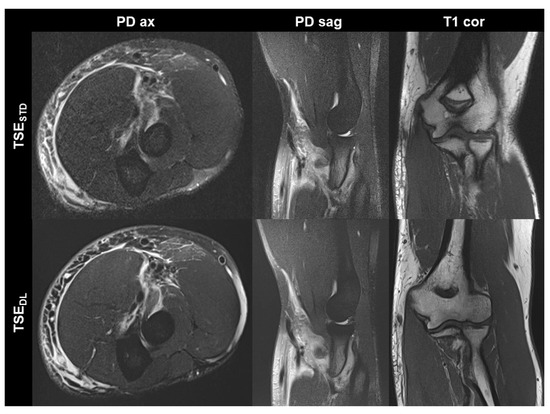

Figure 1. Non-contrast elbow MRI acquired at 1.5 T in a 51-year-old female patient with the institution’s standard turbo spin echo (TSE) sequences (TSESTD, upper row) and deep learning-reconstructed TSE sequences (TSEDL, lower row). Increased edge sharpness in the TSEDL images is primarily seen in the coronal and sagittal T1-weighted sequences (T1 cor and T1 sag). In the fat-saturated coronal and axial PD-weighted images (PD cor and PD ax) the DL reconstruction shows decreased noise.